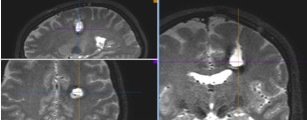

NEURONAVIGATION + IONM

Trans-sulcal Approach

Pre-operative

Post-operative